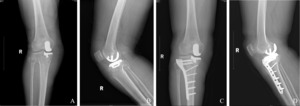

A 64-year-old female patient presented with a history of right knee joint pain lasting over two years. Preoperative physical examination and imaging studies confirmed medial unicompartmental knee osteoarthritis. On August 16, 2022, she underwent right medial UKA using the Oxford Unicompartmental Knee System, Phase 3 (Zimmer, Warsaw, USA). The procedure involved implantation of an A-size tibial plateau and an extra-small femoral condyle prosthesis. Postoperative radiographs on day one confirmed proper prosthesis alignment with no signs of fractures. Standard rehabilitation was initiated, and the patient was able to walk with a walker on postoperative day two. Early postoperative recommendations included avoiding strenuous activities to minimize loading on the lower limb. Follow-up evaluations indicated satisfactory knee function, with no significant discomfort and a good range of motion (Figure 1).

On April 3, 2023, the patient underwent ORIF. A lateral approach to the proximal tibia was used, with an incision approximately, providing adequate exposure of the lateral tibial plateau. Following reduction of the fracture, an anatomically contoured locking plate was applied to the proximal tibia. Intraoperative evaluation confirmed stable fixation, and the prosthesis showed no signs of loosening. Postoperative radiographs on day one confirmed proper plate and screw positioning, as well as the stability of the prosthesis (Figure 2). Monthly follow-up radiographs were obtained, and weight-bearing activities were restricted for the first six weeks. At three months postoperatively, the patient gradually resumed full weight-bearing activities. The recovery was uneventful, and follow-up radiographs at one year postoperatively showed excellent fracture healing, with no visible fracture line, a stable prosthesis, and normal knee range of motion without pain (Figure 3).